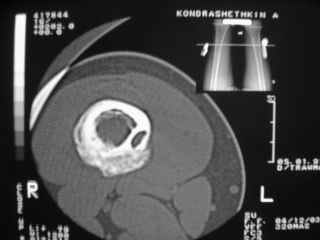

Анамнез практически никакой: в следствие травмы (растяжение связок коленного сустава) от 07.11.2004 выполнены Rg-граммы в травмпункте и обнаружено опухолевидное образование. Первичные Rg-граммы я не публикую, так как они заметно худшего качества, да и динамики за прошедшие три недели не отражают. Болевой синдром купирован в течение трёх дней. В настоящий момент мальчика ничего не беспокоит. Ходьба не нарушена, опухоль пальпируется с трудом по задней поверхности в н\3 правого бедра, пальпация безболезненна, объем движений в суставах правой нижней конечности полный и симметричный. Кожа над опухолью не изменена. В нашей клинике проведено дополнительное обследование: общие анализы крови и мочи, биохимия крови без особенностей. Выполнены Rg-граммы на цифровом Siemens обычные и продольные томограммы срезами 3-5 мм, а также компьютерная томография поперечными срезами по 5 мм. Прошу обратить внимание, что на приведённых томограммах видны две полости 10х15 мм и 15х60 мм. Также имеются два опухолевидных образований наслаивающихся друг на друга: уплощённое и вытянутое 10х100 мм и элипсовидной формы 15х30 мм. Это хорошо заметно на фото a_1.jpg c_1.jpg и d_1.jpg. Плотность внутри полостей 125% от плотности костномозгового канала, плотность наружного опухолевидного образования 55% от плотности кортикального слоя. Также отмечается линия перелома по центру наружного опухолевидного образования. Исходя из полученных данных мнения в плане диагноза несколько разделились от 1)сочетания кортикальной фиброзной дисплазии и латентно протекавшего маршевого перелома н\3 правого бедра до 2)остеосаркомы. В отношении первого варианта не сходится отсутствие клиники при переломе такой крупной кости как бедро, второй вариант вообще оставлю без комментария, ибо некомпетентен. Хотелось бы услышать мнения коллег, с удовольствием ознакомлюсь с любыми предположениями и замечаниями. С уважением, Александр Е. Клоков Отделение детской ортопедии и травматологии БСМП г. Мурманска.